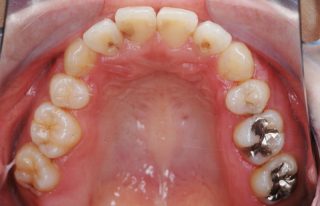

スピード矯正のケースです。

他院で3年以上矯正装置をつけていないとダメという診断で、スピード矯正を希望して来院。3年が半分になれば良いとのことでしたので、スピード矯正対応となりました。ワイヤーの治療期間は、当院では1年3か月でした。患者様からもあっという間の矯正治療でしたと満足のお言葉をいただきました。時間がない方は、是非お試し下さい・・・スピード矯正。通常の矯正より確実に早いです。

- ①治療期間:1年3カ月(約30回)

- ②費用:約115万円(税別)